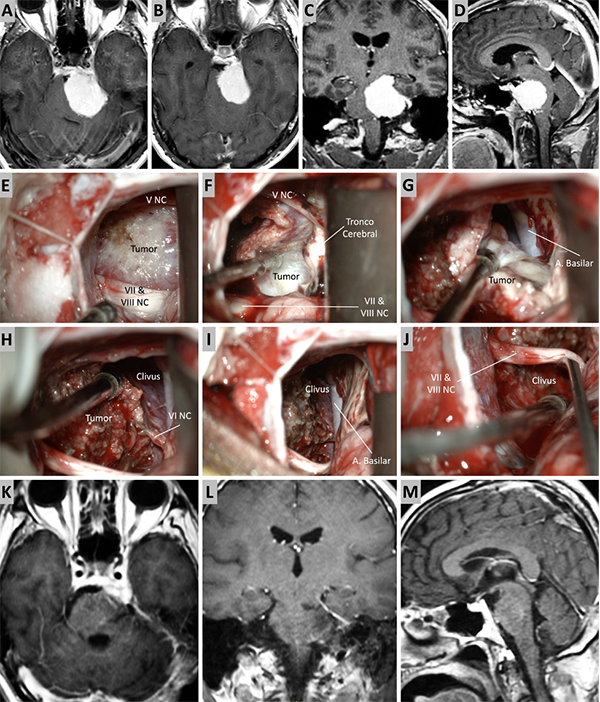

Figura 5. Caso ilustrativo #3. A-D. Resonancia que muestra MRPC con implantación clival. E-J. Se realiza un abordaje retrosigmoideo, consiguiendo la liberación del complejo VII-VIII del tumor y su resección completa. K-M. Resultado imagenológico postquirúrgico.

Figura 6. Caso ilustrativo #4. Meningioma de la MRPC con implantación petrosa anterior. El paciente presentaba neuralgia del trigémino atípica derecha. A-D. Imágenes por RMN pre operatorias. E-J. Se realiza un abordaje retrosigmoideo consiguiendo la resección total del tumor. K-M. Con ayuda de endoscopio y lente con angulación de 30º se inspecciona el área sin encontrar remanente tumoral. Se observa liberación del nervio trigémino. K-M. RMN postoperatoria que muestra resección total.